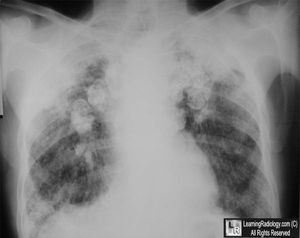

What's the name of this sign??

1. Hair-on-end 2. Deep sulcus sign 3. Angel wing sign 4. Eggshell calcification 5. Homan's sign

Eggshell calcification, maybe silicosis?

Eggshell calcification

Eggshell..may be silicosis